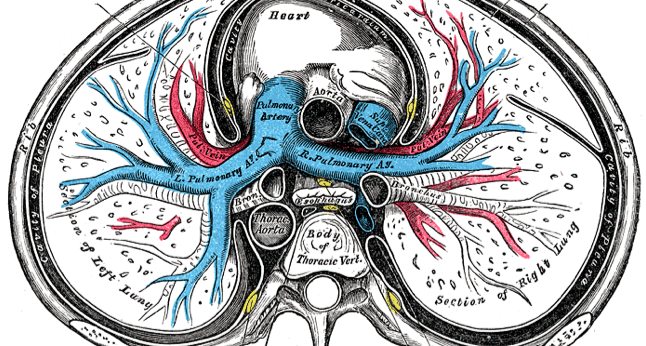

Laren Tan, MD; Samuel Louie, MD

Few signs cause more apprehension than the coughing or expectoration of bright red blood originating from the lungs, known as hemotpysis.

05/08/2014